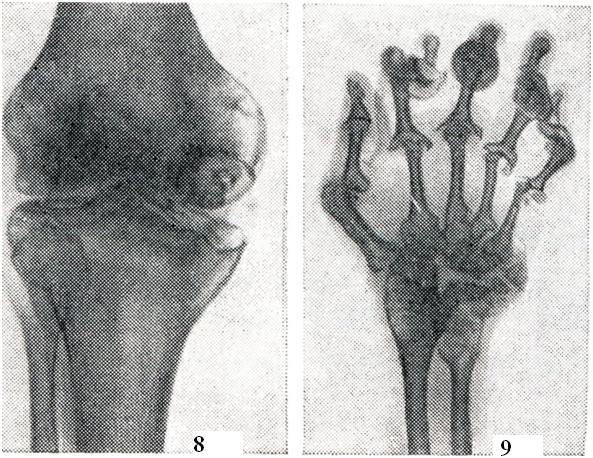

Наиболее характерен метастатический гонит (моноартрит с острым и подострым течением). Морфологически острый гонит может быть серозным или гнойным, подострый — серозно-фибринозным. При всех формах отмечаются мучительные боли, высокая температура, тяжелое общее состояние больного. Развитие патологических изменений в суставе резко выражено: быстро развивается деформация, сгибательные контрактуры (рис. 14), мышечная атрофия. Показатели лабораторных исследований говорят об активности воспалительного процесса. В пунктате можно обнаружить гонококки. При неправильном или запоздалом лечении быстро развивается выраженная деструкция суставных элементов и анкилоз.

Сифилитический артрит (arthritis syphilitica) может появляться при врожденном и во всех стадиях приобретенного сифилиса. В наст, время встречается редко. При врожденном сифилисе может быть несколько форм артрита: сифилитический остеохондрит Парро, синовит коленных суставов со значительным количеством выпота и шарообразной формой коленных суставов — суставы Клаттона, сифилитический дактилит и другое. Артрит в первой стадии сифилиса может проявляться кратковременной поли-артралгией. Во второй стадии также отмечаются боли в суставах, костях и мышцах, усиливающиеся ночью. Иногда наблюдается полиартрит летучего характера, при котором не помогают салицилаты, но хороший эффект дает лечение пенициллином. В третьей стадии может быть гуммозный артрит крупных суставов, который проявляется гидрартрозом с выпячиванием заворотов синовиальной оболочки (рис. 16). На рентгенограммах могут наблюдаться признаки артроза (вторичный артроз). Если процесс локализован в одном суставе, его внешне трудно отличить от костно-суставного туберкулеза. Сифилитический артрит в четвертой стадии проявляется табетической артропатией, которая чаще всего поражает коленный сустав и отличается большими структурными изменениями при сохраненной функции.

Туберкулезный артрит является хроническим заболеванием, протекающим с признаками общей интоксикации и местными симптомами синовита. При рентгенологическом исследовании в эпифизарной части кости можно обнаружить ограниченный очаг декальцинации (рис. 17), иногда в виде костного дефекта, секвестрацию и сужение суставной щели.

Псориатический полиартрит (polyarthritis psoriatica) развивается чаще у больных, уже имеющих кожные проявления псориаза, в среднем через 6 лет после их появления, но иногда может им предшествовать или появиться одновременно. Псориатический полиартрит в наст, время выделен в самостоятельную нозологическую форму. Клиническая картина его чрезвычайно похожа на ревматоидный артрит, однако имеет некоторые особенности: 1. Почти всегда поражаются дистальные межфаланговые суставы пальцев рук. Одновременно, как правило, поражаются ногти (рис. 18). 2. В процесс вовлекается обычно небольшое количество других периферических суставов (2—3, редко больше), при этом поражение носит асимметричный характер. В тяжелых случаях суставной процесс может быть генерализованным. 3. Поражаются межпозвонковые суставы поясничной области и крестцово-подвздошные суставы, где могут развиваться анкилозы, поэтому псориатический полиартрит нужно дифференцировать с болезнью Бехтерева. 4. Течение обычно ремиттирующее, резкие обострения часто чередуются с частичными ремиссиями. При этом отмечается определенный параллелизм с кожными проявлениями псориаза.

На рентгенограмме кистей часто обнаруживается лизис дистальных фаланг пальцев (мутилирующий артрит), что характерно и для склеродермии. В остальном рентгенологическая картина мало отличается от картины при ревматоидном артрите.